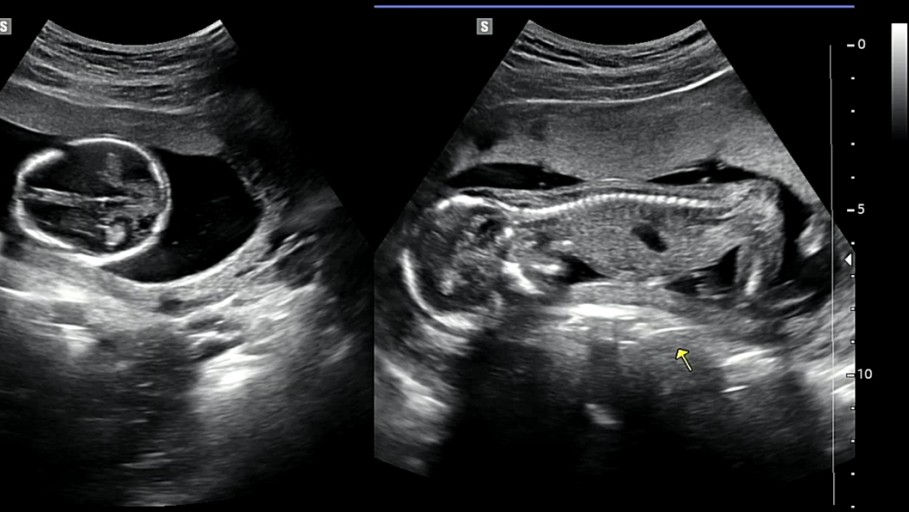

헌법재판소는 오늘(28일) 의료법 20조 2항에 대한 판단을 내리면서, 임신 32주 전까지 의료인이 태아의 성별을 알려주는 것을 금지한 현행 의료법은 헌법에 어긋난다고 판결했습니다.

현재 의료법 제20조 2항은 임신 32주 이전에 의료인이 태아의 성별을 알려줄 수 없도록 규정하고 있었습니다. 이는 남아 선호 사상에 기인한 여아 낙태 예방을 위한 조항으로 설계되었습니다.